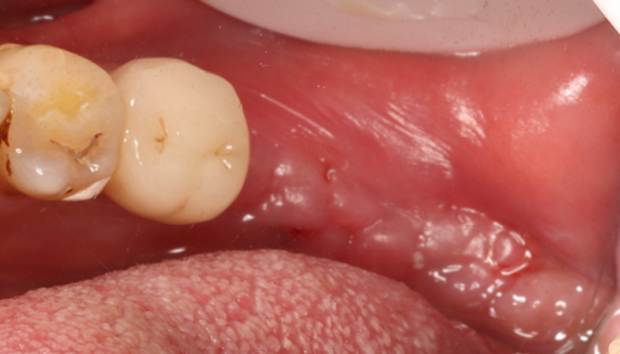

2. A follow-up examination was conducted three months after tooth extraction upon complete wound healing, and implant restoration was initiated.

Post-extraction wound healing status